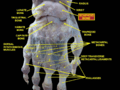

Scaphoid shown in yellow. Left hand. Palmar surface.

The scaphoid is situated between the proximal and distal rows of carpal bones. It is located on the radial side of the wrist, and articulates with the radius, lunate, trapezoid, trapezium and capitate.[1] :176 Over 80% of the bone is covered in articular cartilage.[2]